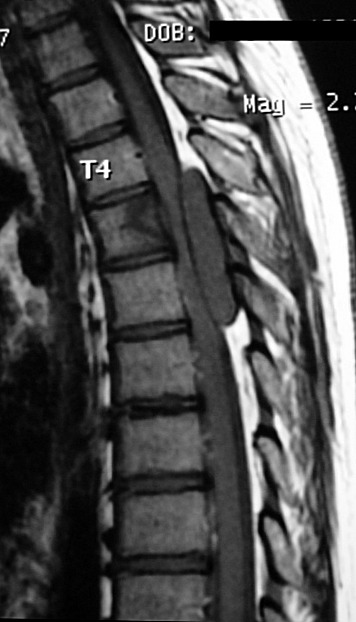

ГМ. СМ. Ганглионейробластома. +

Ганглионейробластома